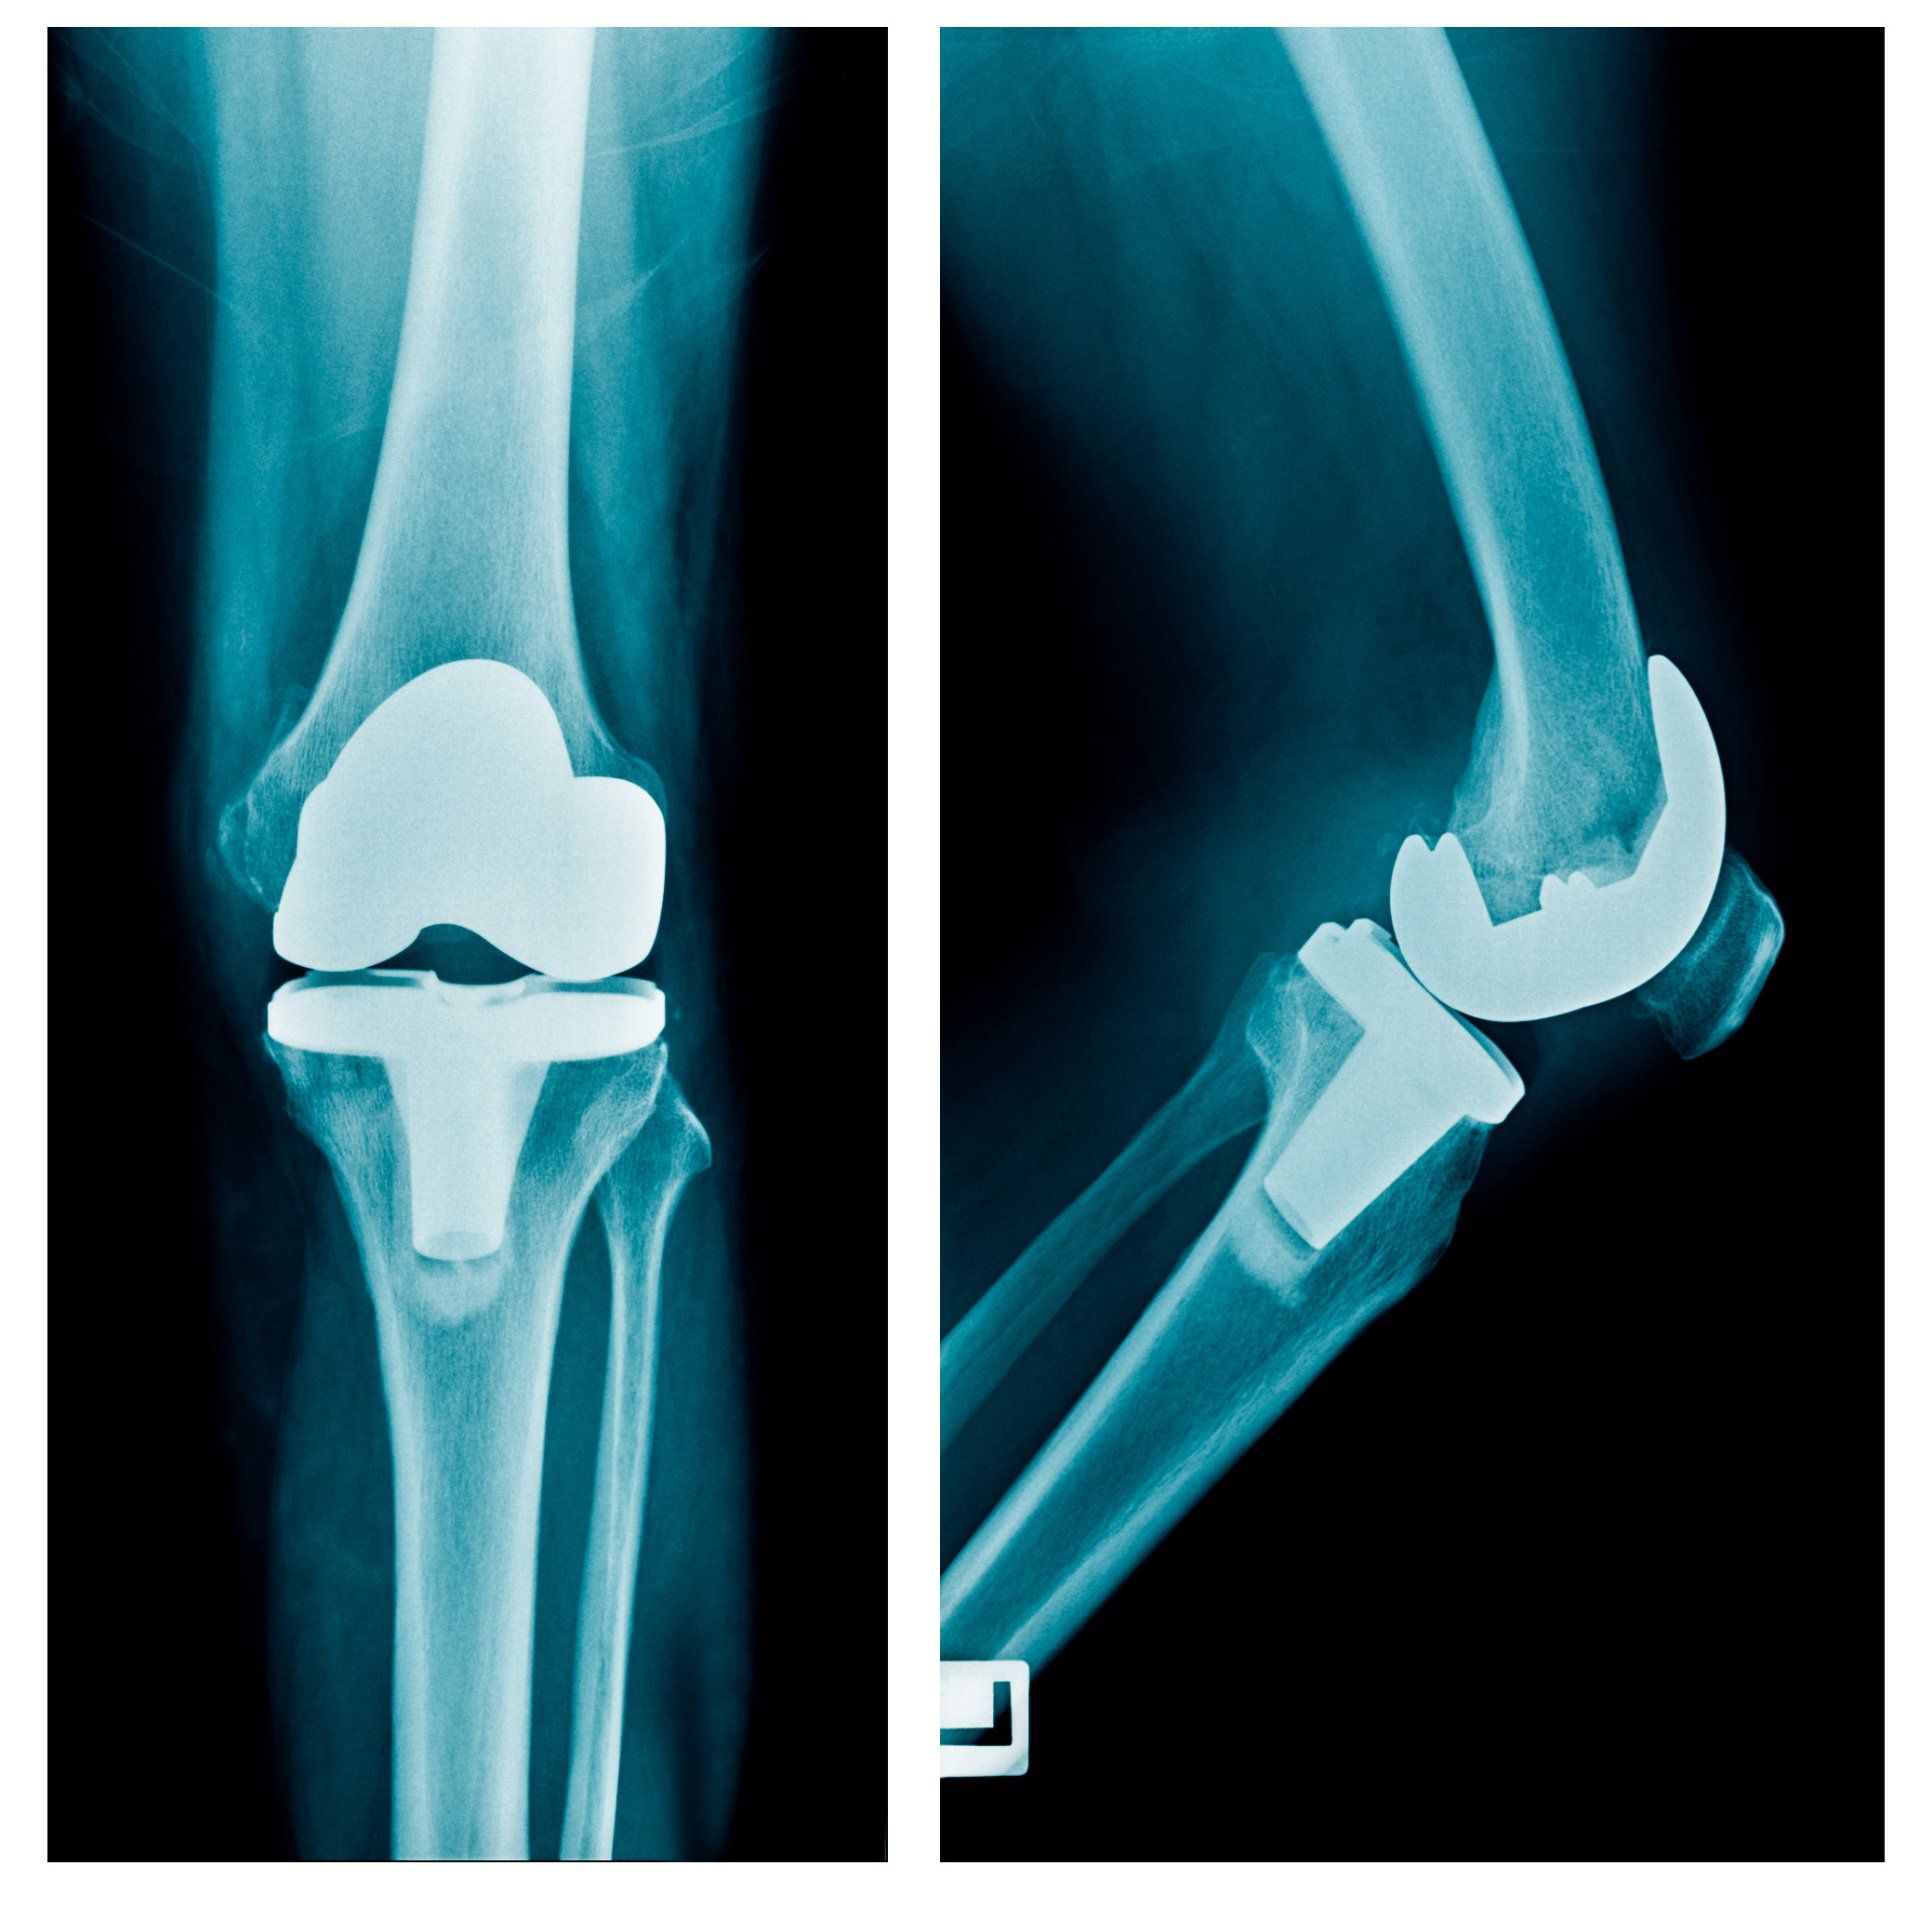

- Ακτινογραφίες:

- Προσθιοπίσθια λήψη: βοηθά να επιβεβαιωθεί ότι το έσω και το έξω διαμέρισμα του γόνατος δεν προσβάλλονται από σημαντική αρθρίτιδα

- Πλάγια λήψη: αξιολογεί το βαθμό φθοράς του επιγονατιδομηριαίου διαμερίσματος

- Καθ’ εφαπτομένη λήψη: βοηθά στην απεικόνιση του βαθμού φθοράς μεταξύ της επιγονατίδας και του μηριαίου